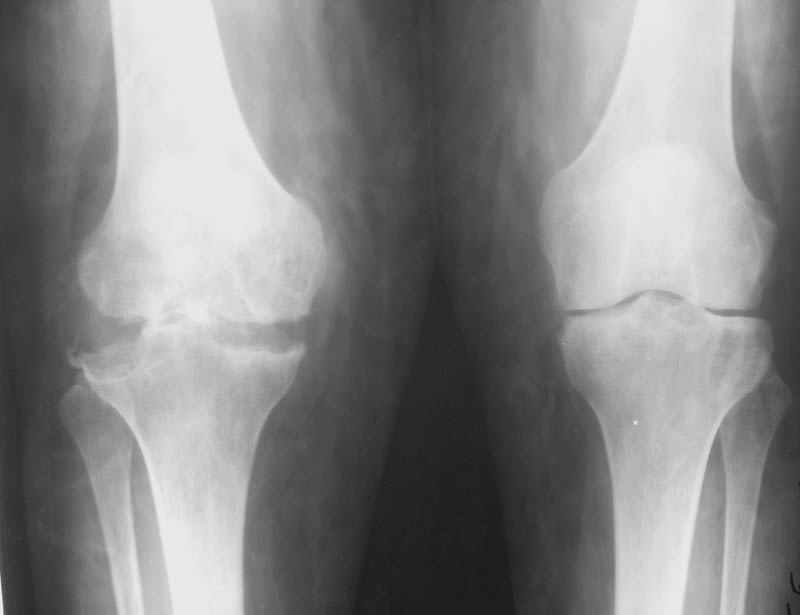

Уважаемые коллеги! Женщина, 28 лет. Страдает ревматоидным полиартритом, гормонозависима. 6 месяцев назад перенесла тотальное эндопротезирование левого тазобедренного сустава по поводу протрузионного коксита.

Использована цементная версия с пластикой дна впадины измельченной аутокостью и гранулами гидроксиапатита. Субъективное улучшение после операции. Улучшилось и стабилизировалось общее состояние. В настоящее время затруднено передвижение из-за поражения правого коленного сустава. Болезненный и <болтающийся> сустав. Предполагается замена сустава протезом без сохранения задней крестообразной связки. Возможные варианты? Заранее благодарю! С уважением, А.В.Владзимирский Донецкий НИИ травматологии и ортопедии Донецк, Украина